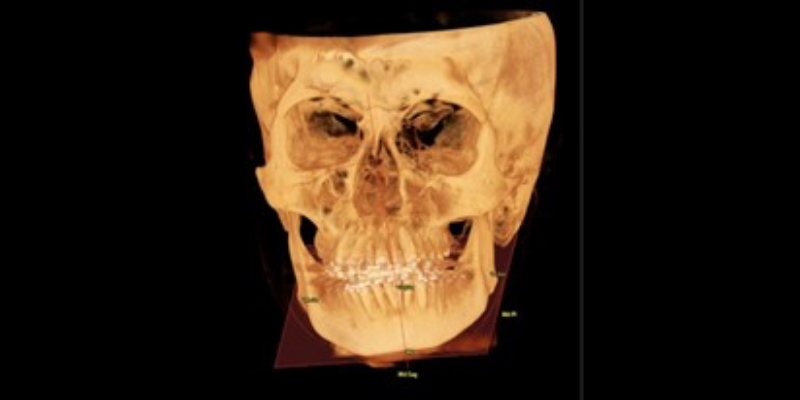

Asymmetry in ramus length indicates abnormal growth in the condylar region or a history of trauma. Oftentimes, this is benign; however, it can harm occlusion and facial esthetics. This condition can also cause changes in pharyngeal airway morphology, which has been shown to improve following orthognathic surgery. Visualizing and measuring the ramus length is helpful in a differential diagnosis.

Transverse Dimension

The transverse dimension is also critical to visualize and understand, as deficiencies can result in sleep disorders, malocclusion, tooth wear, and improper growth. Practitioners can measure the maxilla and mandible to understand better their growth relationship (Fig. 7). The ideal relationship would be a measurement of maxilla plus 5.0 mm compared to the mandible. The image also demonstrates the patient’s inability to get their tongue to the palate.

How the tongue fills this space is an excellent indicator of narrow arches and a likely tongue-tie, which affected growth. Recognizing transverse dimension issues early can produce very predictable corrections through expansion. With the introduction of TAD expanders and surgical intervention, adults can correct these issues improving occlusion, sleep, and overall health.